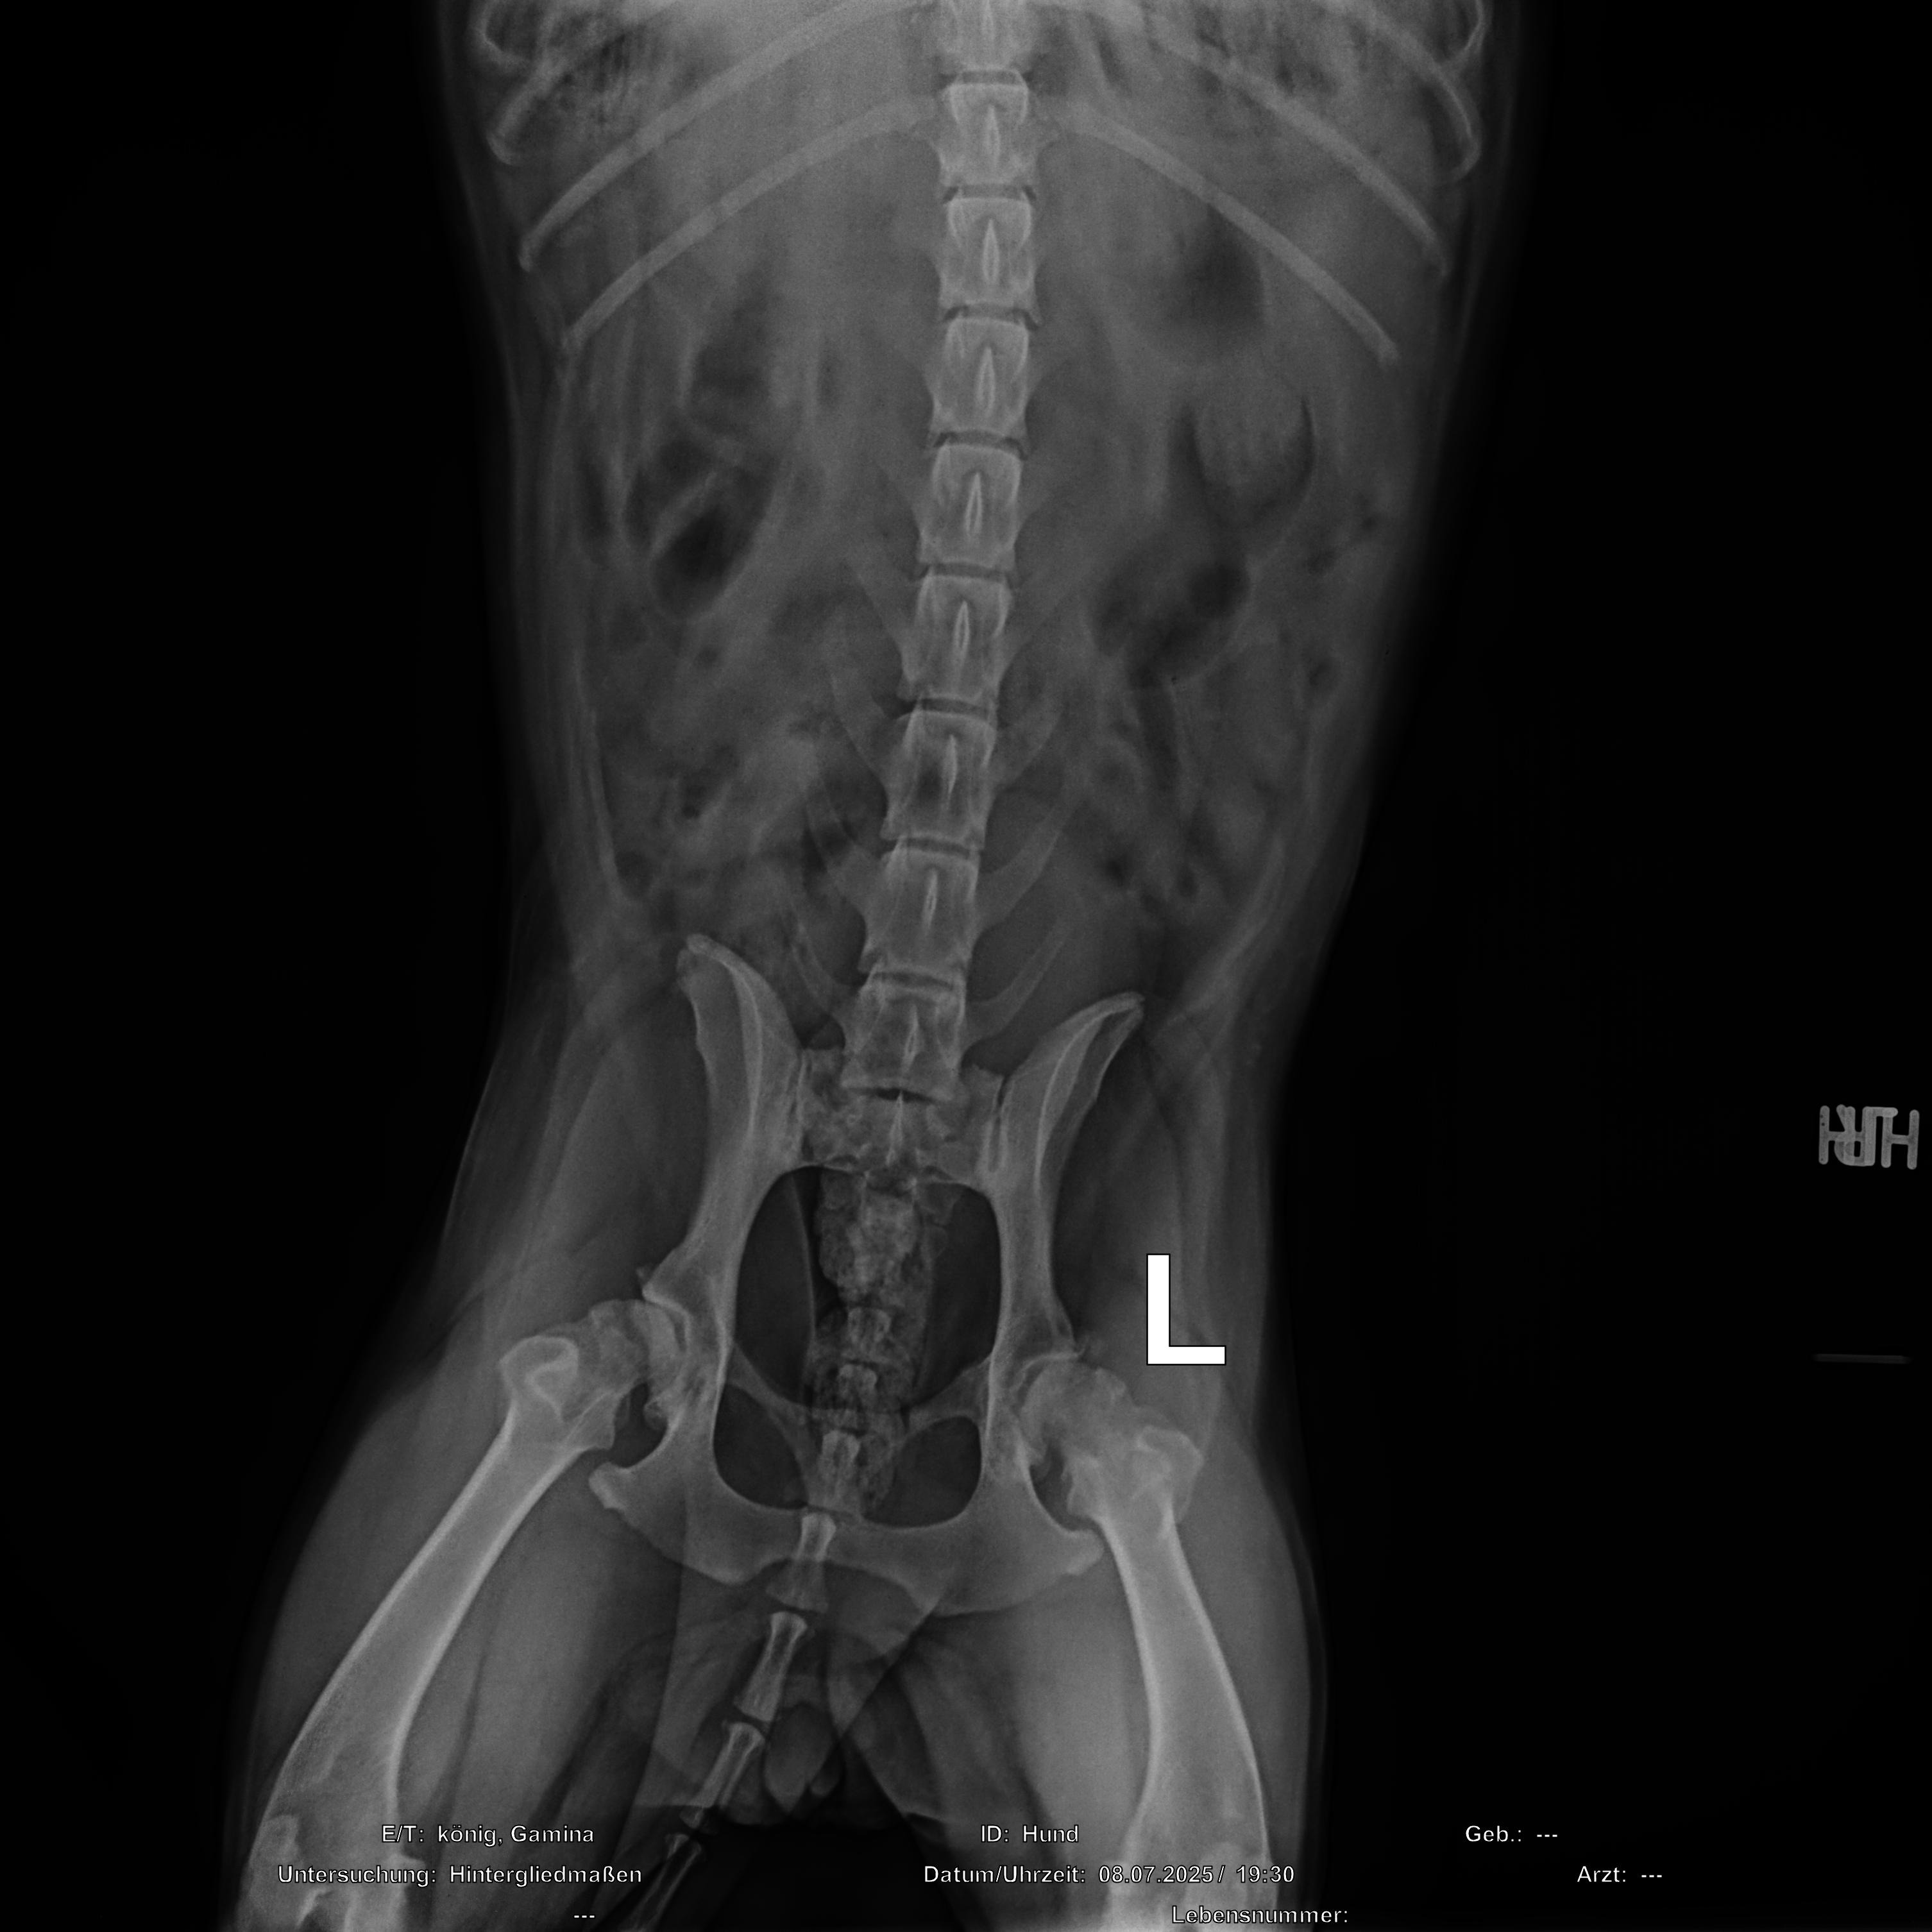

Nach einer ausführlichen Untersuchung wurde dann ein Röntgen gemacht bei dem sich zeigte, dass beide Hüften unserer Maus komplett zerstört sind und sie beidseitig ein neues Hüftgelenk braucht.

Bei den Bildern findet ihr den Kostenvoranschlag für eine der beiden benötigten Operationen und das aktuelle Röntgenbild.

After a thorough examination, an x-ray was taken, which revealed that both of our little girl's hips were completely destroyed and she needed a hip replacement on both sides.

In the pictures you will find the cost estimate for one of the two required surgeries.